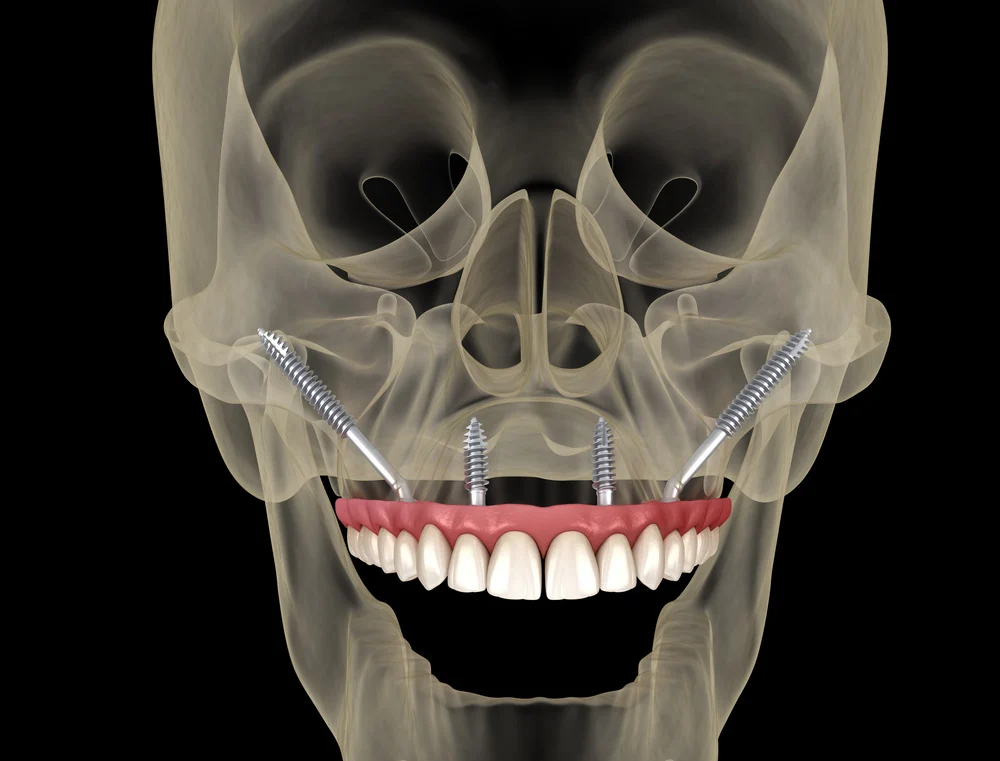

- Posizionamento inclinato nell’osso zigomatico: gli impianti vengono inseriti con un’inclinazione che parte dalla cresta alveolare del mascellare e raggiunge lo zigomo. Questo consente di ottenere una stabilità immediata anche nei casi in cui il mascellare sia completamente atrofico.

- Lunghezza superiore rispetto agli impianti standard: per raggiungere l’osso zigomatico, gli impianti devono attraversare una porzione significativa del viso. Per questo motivo la loro lunghezza varia dai 30 mm fino a oltre 55 mm, contro i 10-18 mm degli impianti tradizionali.

Nella chirurgia implantare zigomatica, l’impianto viene inserito con un’inclinazione precisa attraverso il seno mascellare o in modalità extra-sinusale, fino a raggiungere e fissarsi nell’osso zigomatico. Questo approccio evita la necessità di rigenerare osso e permette, in molti casi, il carico immediato della protesi dentale. - Supporto per protesi fisse